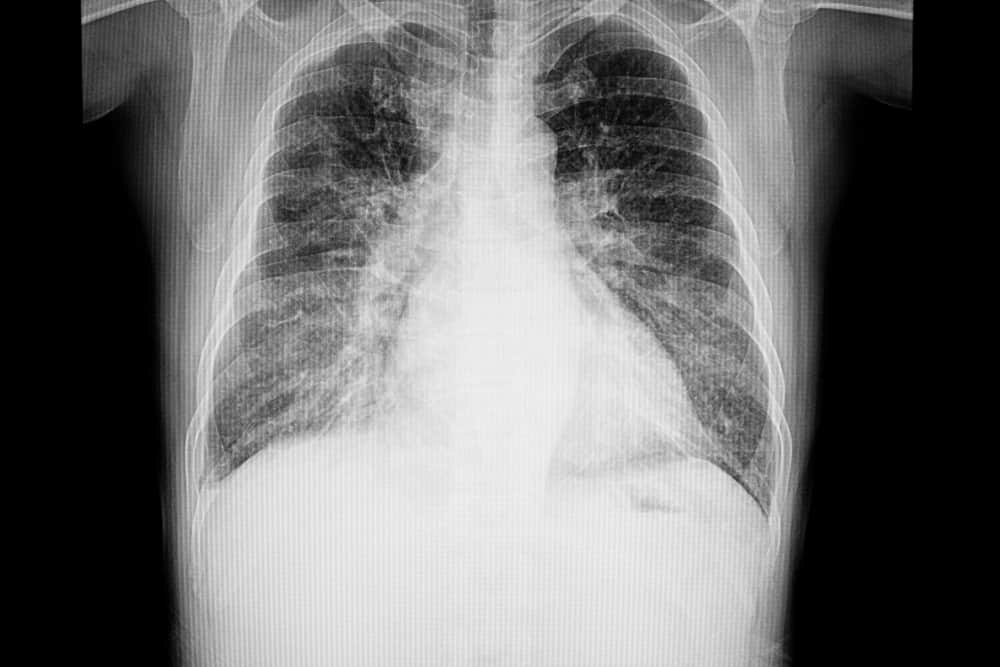

医師は、肺の中または周囲に液体があるかどうかを確認したり、心臓の大きさをチェックしたりするために、胸部 X 線検査または肺の超音波検査を依頼する場合があります。 CT スキャンを注文することもできます。